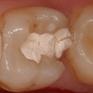

molaire avec une ancienne obturation déféctueuse

après ablation de la vieille obturation

nouveau composite en place